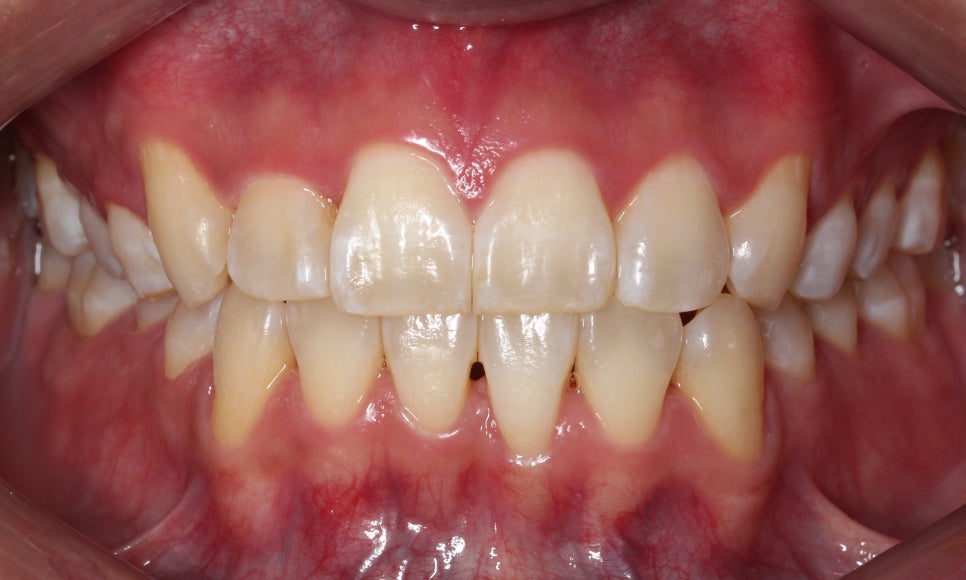

배열이 처음보다 훨씬 좋아졌습니다.

차이가 조금 더 느껴지실까요 ?^^

마찬가지로 좌 before, 우 after입니다.

이렇게 보면 훨씬 개선된 것이 눈에 띄시죠?^^

부분교정으로 진행하는 것이다 보니

전체 교정보다 완벽할 순 없지만,

환자분께서 매우 만족하셨습니다.

가장 신경 쓰여하셨던 #12 치아가

앞으로 나오면서 훨씬 가지런해지고

아래 치아 치축도 개선되면서

더욱 정돈된 이미지를 가지셔서

크게 만족하셨습니다.

송곳니 위치와 어금니 교합만 좋다면

부분교정만으로도

위와 같이 충분히 좋은 결과를 보실 수 있습니다.